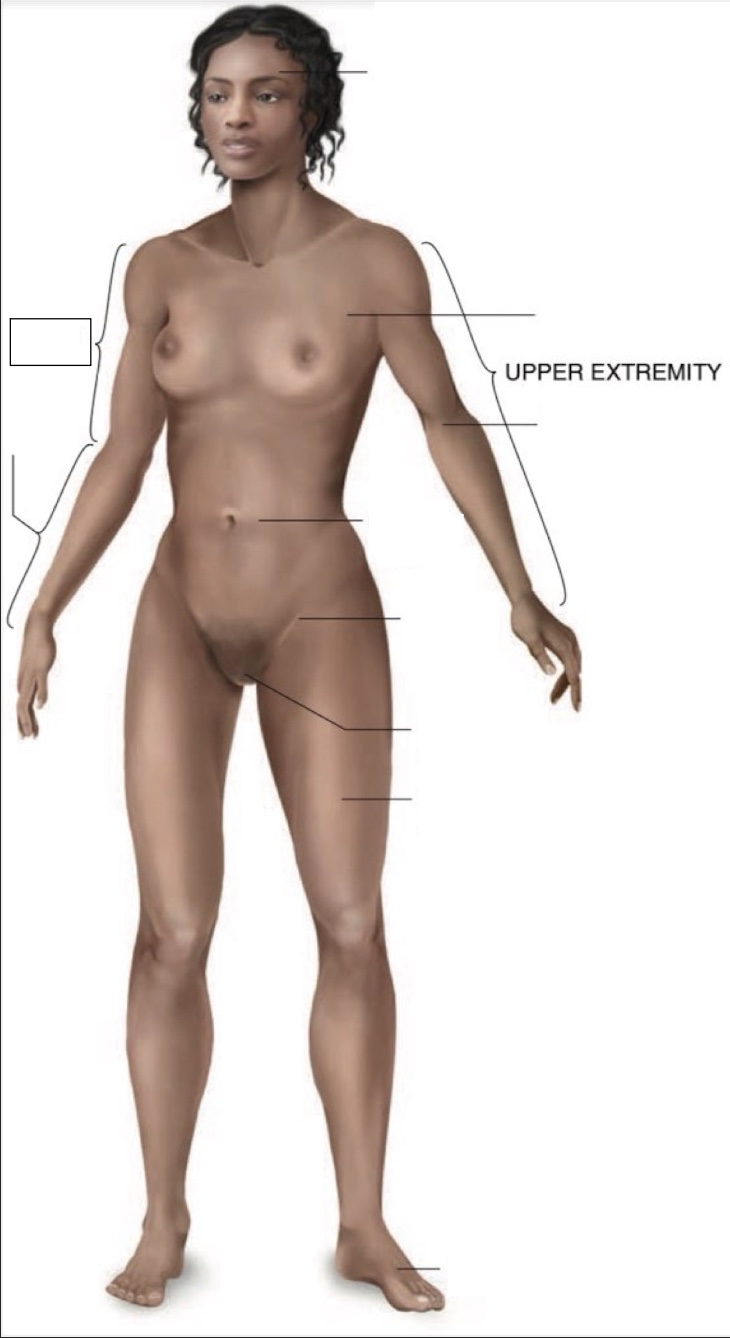

Cranial region

thoracic region

umbilical region

inguinal region

genital region

femoral region

dorsum of foot

arm

forearm

cubital region

Torso

Inferior

Midline